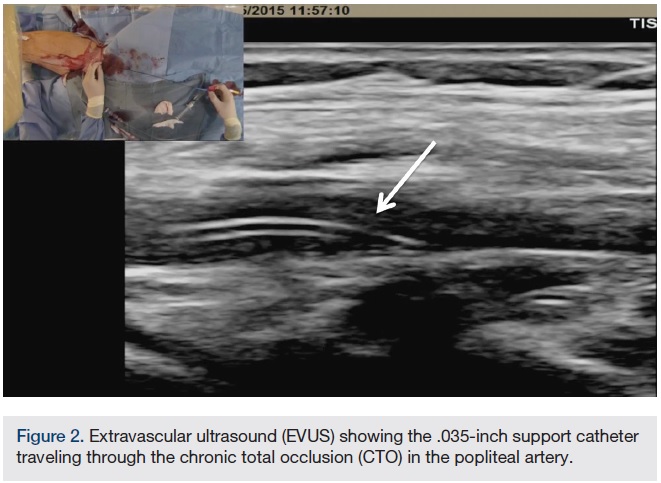

CTO crossing. The use of ultrasound (US) in gaining access to any vascular bed has been shown to be safe and effective. In addition, it is our experience that extra vascular US (EVUS) can also guide CTO crossing and therapy delivery. In this case, a .035-inch Navicross catheter (Terumo) was used to advance through the CTO in a rotational fashion. EVUS allowed us to guide the catheter and navigate the CTO (Figure 2). We were successful in crossing the CTO in the popliteal and peroneal arteries. Once crossing to the distal peroneal was confirmed (Figure 3), we started preparing for therapy.